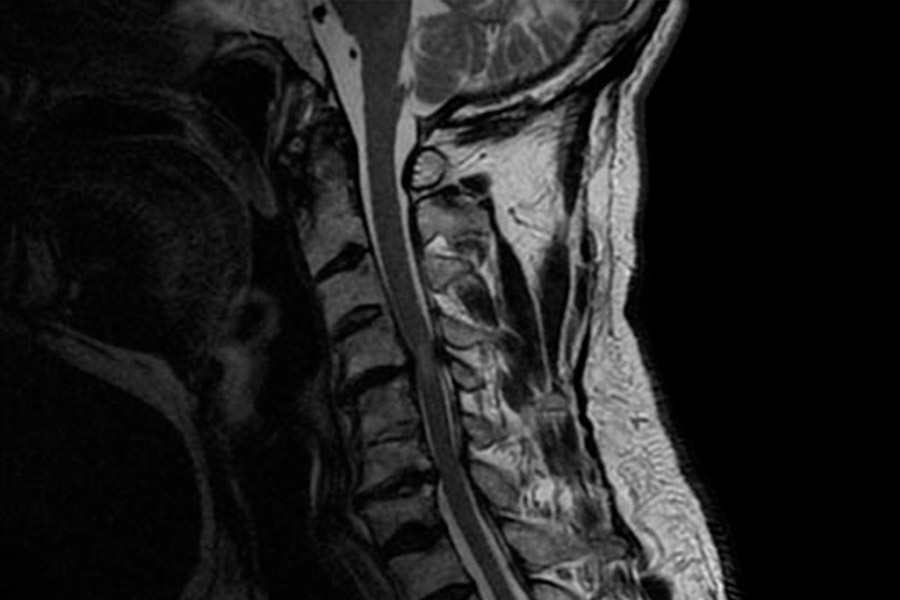

Caso de extrema dificultad en el que podemos ver a un paciente con dolor crónico cervical, parentesias MMSS y hormigueo en los miembros superiores.